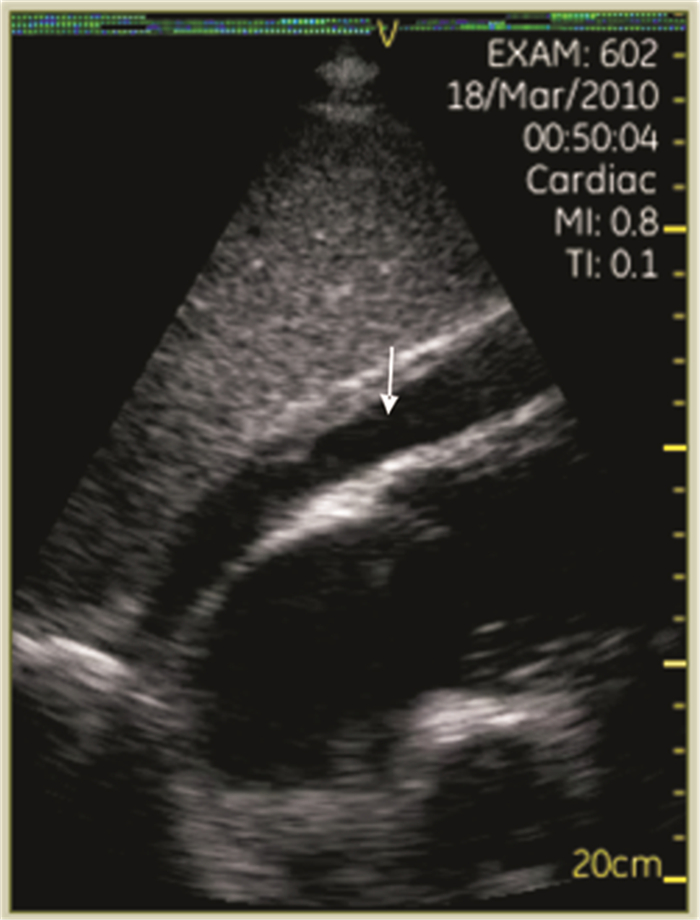

2.1.1 心包无回声区心包腔内出现无回声区(图 1),具体分级见表 1。伴有右心腔塌陷(特别是右室游离壁塌陷)、右房压力升高和/或心脏摆动(钟摆征)时,常见于心脏压塞。

| 图 1 心包积液(箭头示心包无回声区) |